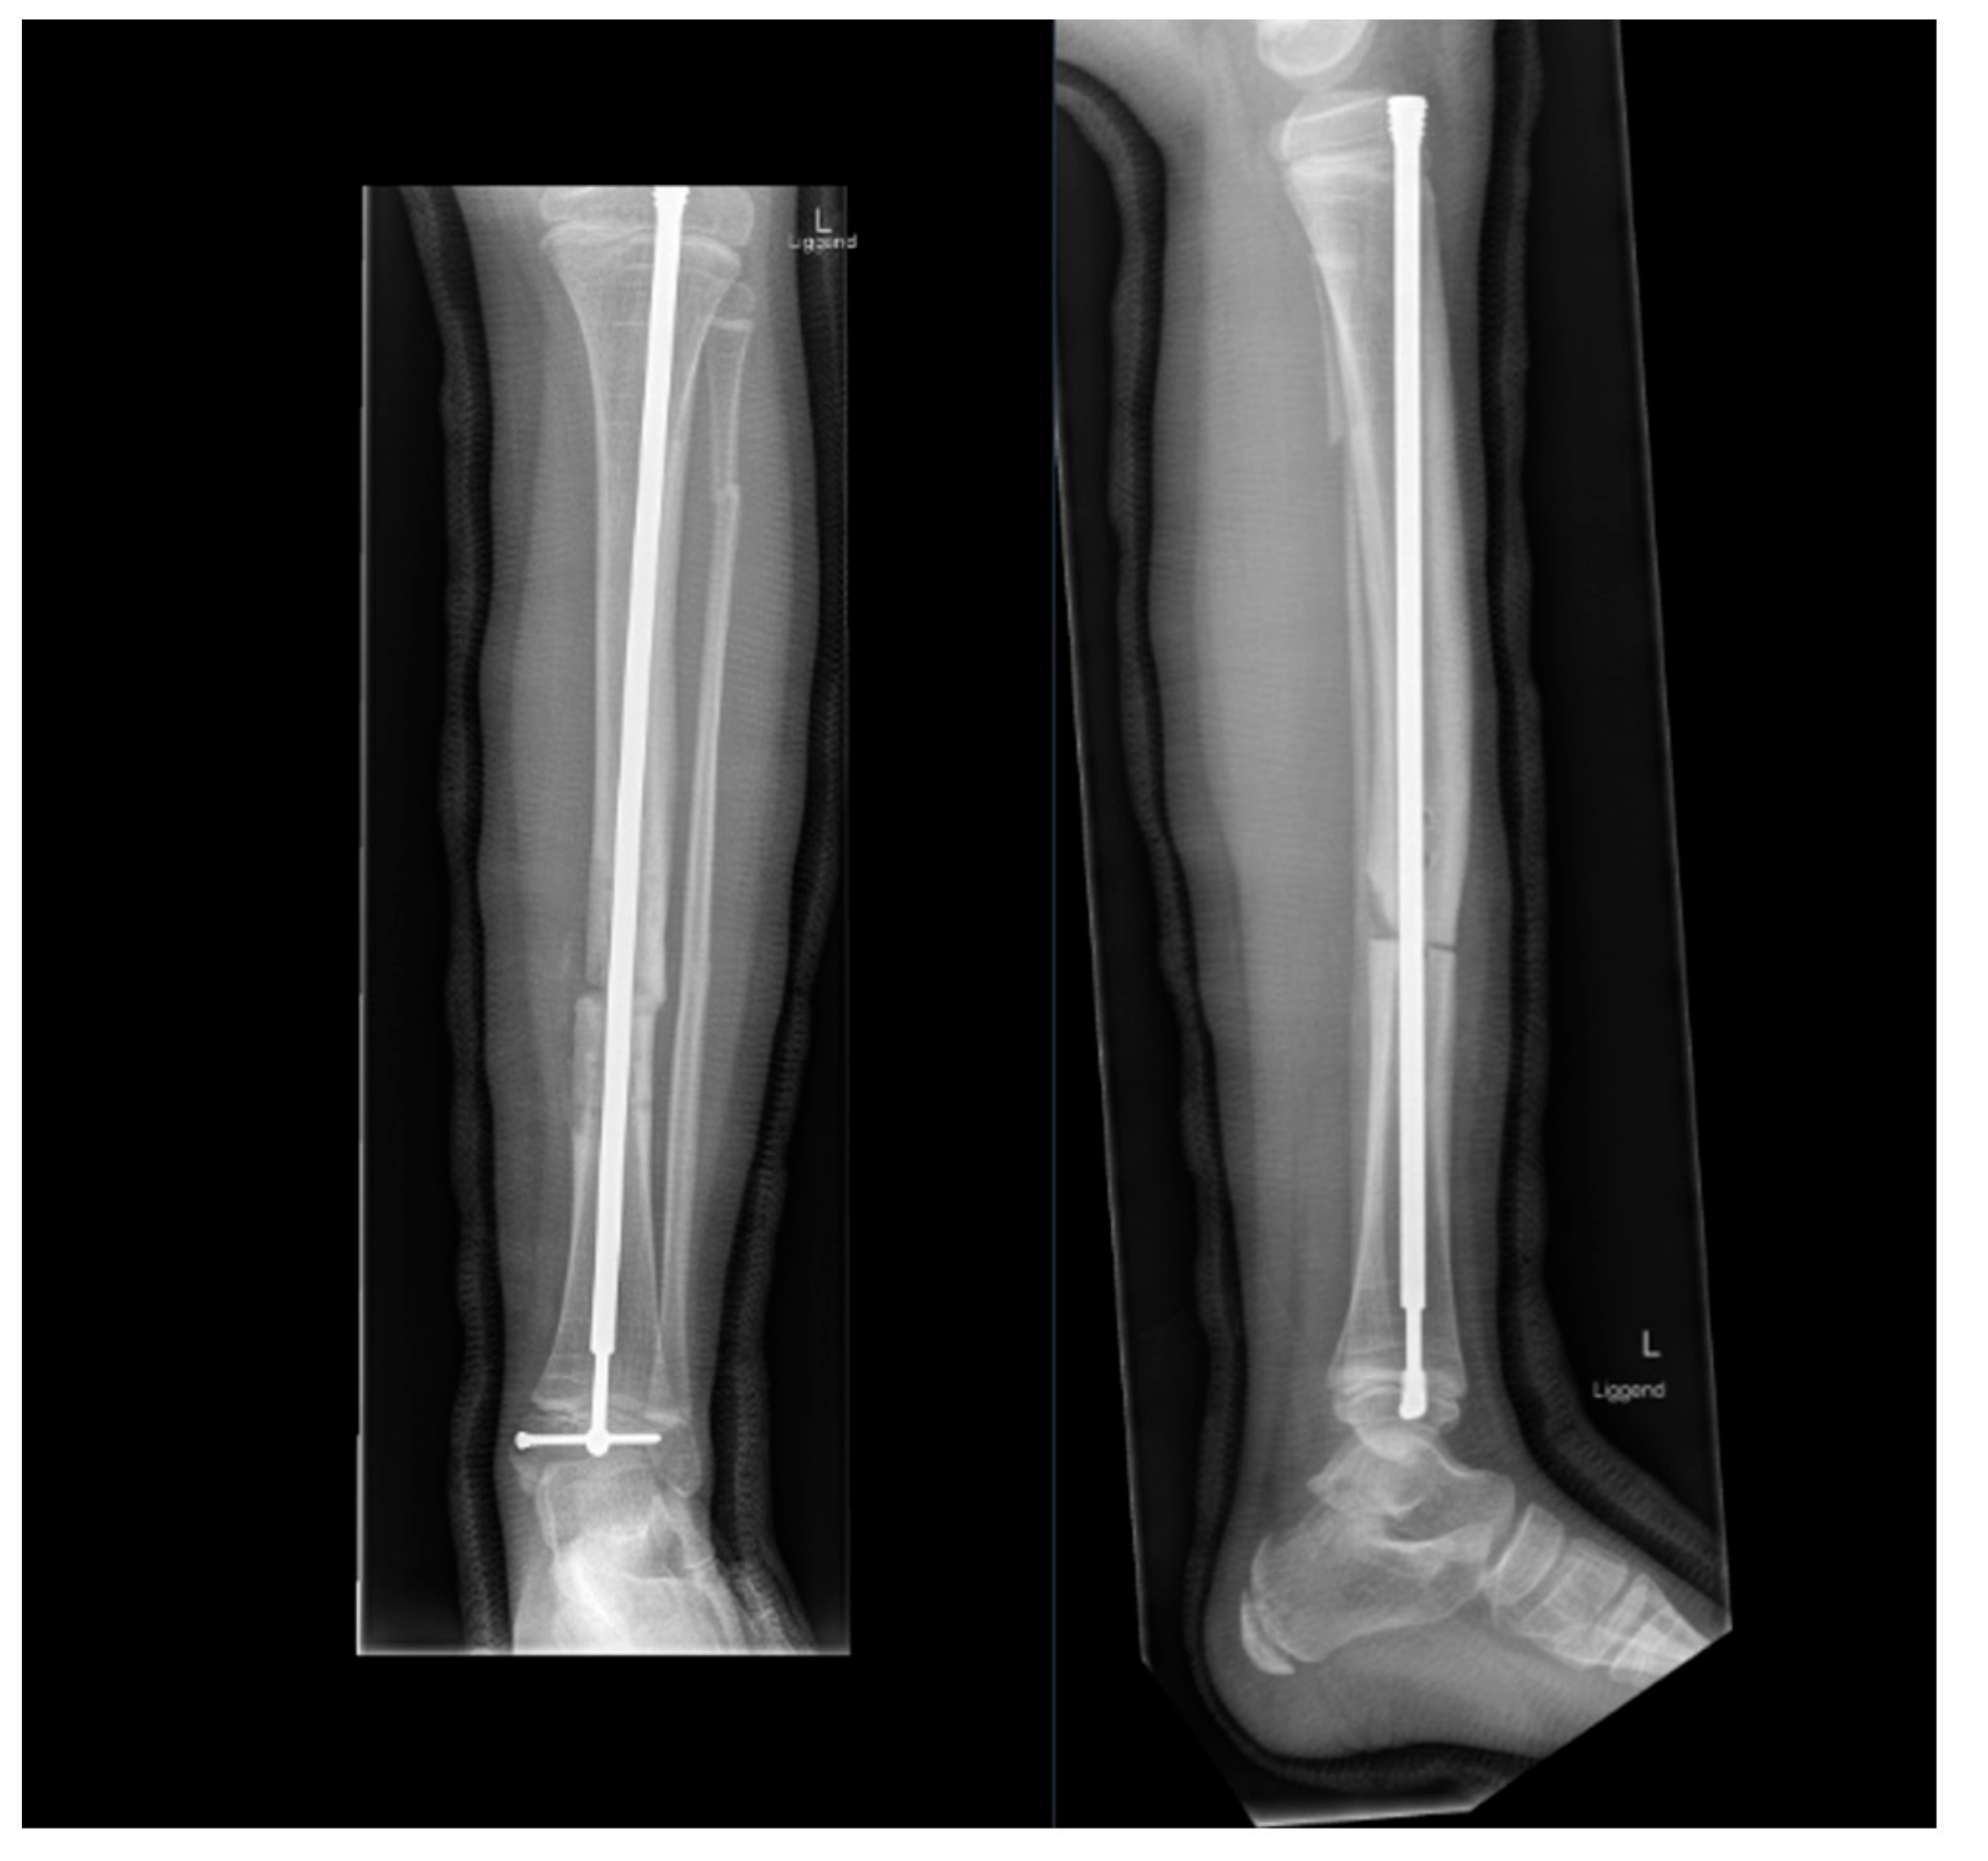

4. Fracture Management

5.3. Preventive Surgery

- Azzam, K.A.; Rush, E.T.; Burke, B.R.; Nabower, A.M.; Esposito, P.W. Mid-term Results of Femoral and Tibial Osteotomies and Fassier-Duval Nailing in Children With Osteogenesis Imperfecta. J. Pediatr. Orthop. 2018, 38, 331–336. [Google Scholar] [CrossRef]

- Sakkers, R.J.; Montpetit, K.; Tsimicalis, A.; Wirth, T.; Verhoef, M.; Hamdy, R.; Ouellet, J.A.; Castelein, R.M.; Damas, C.; Janus, G.J.; et al. A roadmap to surgery in osteogenesis imperfecta: Results of an international collaboration of patient organizations and interdisciplinary care teams. Acta Orthop. 2021, 92, 608–614. [Google Scholar] [CrossRef]